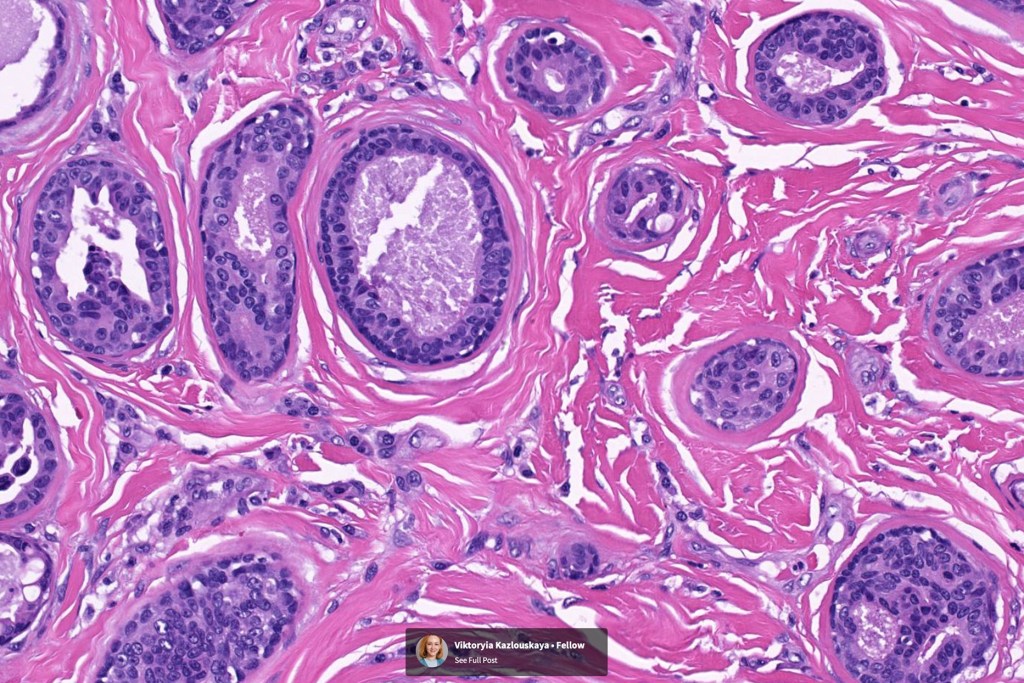

•Circumscribed nodule composed of ducts & cysts embedded in a dense fibrous stroma sometimes associated with lymphoid aggregates/germinal centers

•Ducts lined by double-layered epithelium- small inner, uniform cells with eosinophilic cytoplasm & vesicular/hyperchromatic nuclei with small nucleoli & outer myoepithelial cells

•No pleomorphism and mitoses are sparse of absent

•Pseudo-papillae (devoid of a fibrovascular core) are often conspicuous

Absense of true papillae (i.e with a fibrovascular core)

•Variable cribriform pattern

•Variable clear cell change